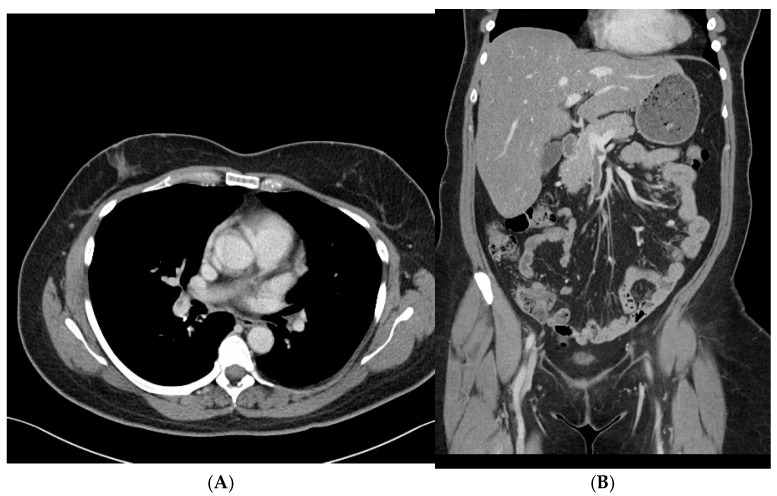

Case presentation: We report a case of S-HIT associated with pulmonary artery embolism, left internal jugular vein, and cerebral vein sinus thrombosis complicated with ipsilateral acute intracerebral hemorrhage.